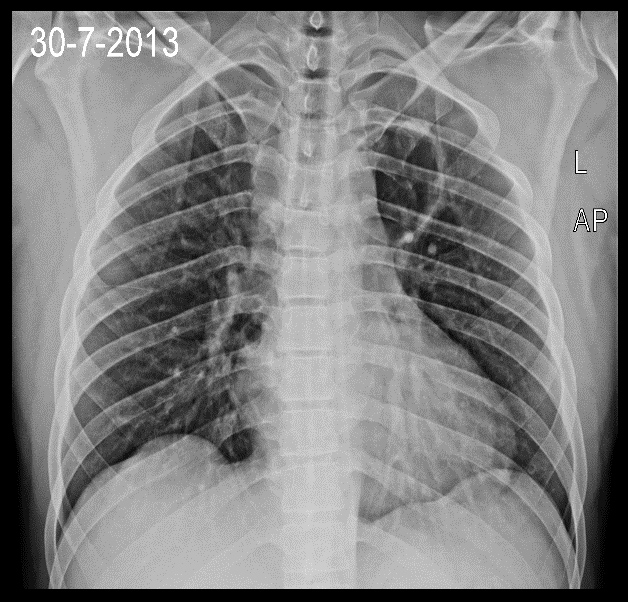

Bei der Suche nach der Ursache wurde auf einem Röntgenbild der Lunge ein etwa 5 cm großer Hohlraum im linken oberen Lungenlappen festgestellt, der am ehesten einem Lungenabszess entsprach. Das Blutbild war unauffällig, MRT des Gehirns und der Wirbelsäule erfolgte, zeigte jedoch keine Abnormalitäten (ein weiteres CT/MRT wäre hilfreich gewesen).

Runder Hohlraum im linken oberen Lungenlappen.